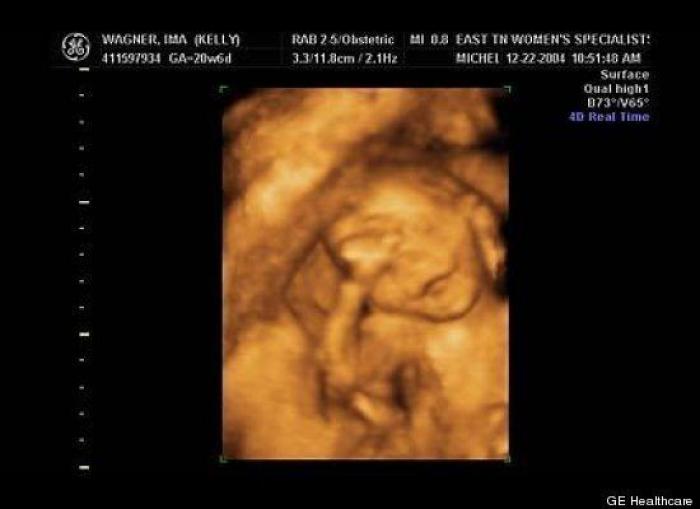

En esta galería puedes ver en fotos como es el desarrollo de un feto de semana en semana:

Desarrollo del feto, en fotos